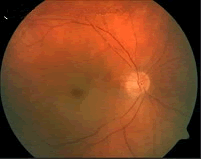

(如图)该种疾病的病因可能是由于()

-

(如图)该疾病的说法正确的是()